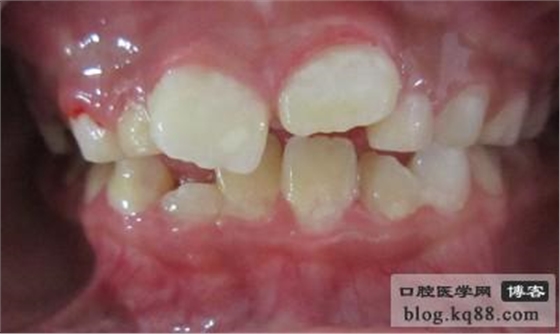

術(shù)后15天復(fù)診圖片資料